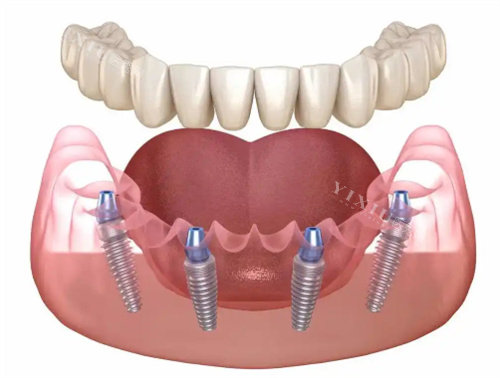

二、种植修复类

国产种植体:1980元起/颗

韩国登腾种植体:2580元起/颗

德国ICX种植体:3680元起/颗

瑞士ITI种植体:5880元起/颗

瑞典诺贝尔PMC种植体:5880元起/颗

全口种植修复:55448元起(含即刻负重方案)